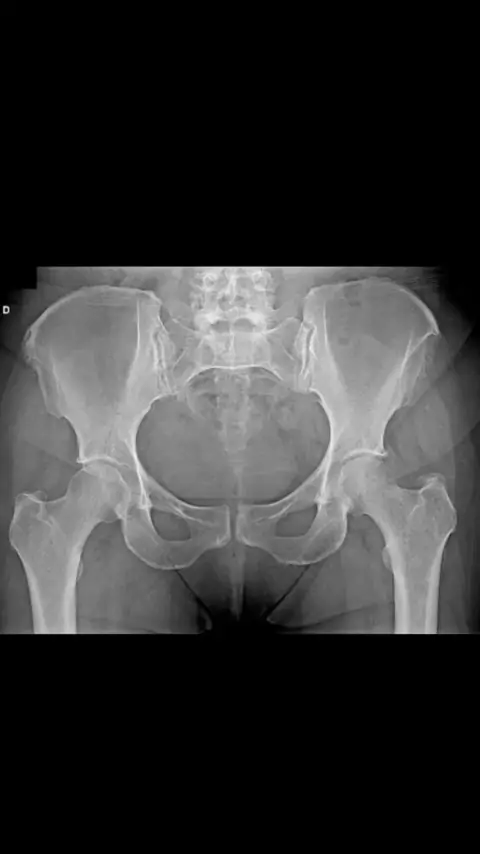

Exame radiológico da Pelve Frente AP. Neste exame o paciente fica em decúbito dorsal com os membros inferiores estendidos e rotacionados cerca de 15 graus medial. O chassi 30/40 ou 35/43 conforme necessário fica na transversal, com a borda superior alinhada ao nível de 5cm superior a crista ilíaca. Raio central (RC) perpendicular ao nível do centro da Pelve na altura das EIAS. #radiologia #radiologiamodernapreparatorioradiologia #radiologiaporamor #radiologiamoderna #radioterapia